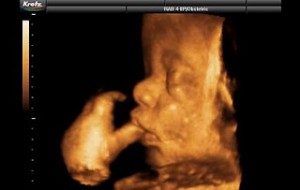

Hamileliğin (Gebeliğin) 35. Haftası Resim ve Video;

Hamileliğin (Gebeliğin) 35. Haftası